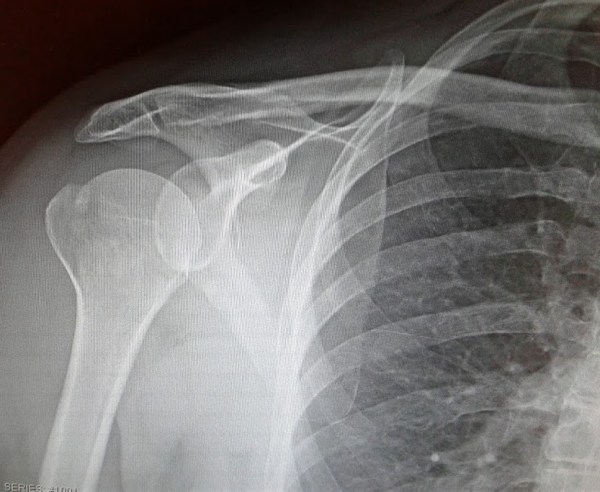

I KNOW THIS PHOTO is not particularly creative, interesting or exciting. I snapped it with my cell phone because I am unable to use my much heavier and bulkier Canon DSLR due to a right shoulder fracture.